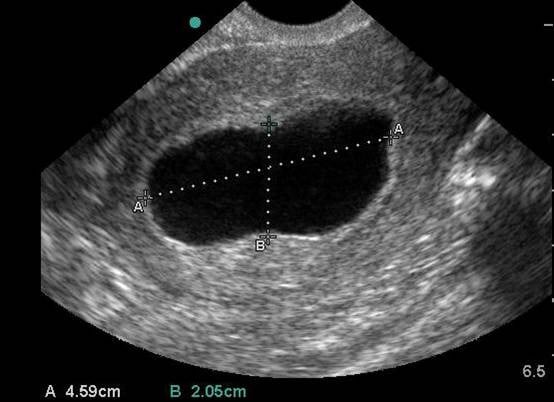

- Twin gestation is becoming more and more common with fertility treatments.

- Monochorionic pregnancy – Single chorionic sac (Video 10)

- Dichorionic pregnancy – Two chorionic sacs separated by a thick wall (Video 11)

Video 10. Transabdominal transverse view of monochorionic triplets

Video 11. Transabdominal transverse view of dichorionic twins. Notice the large septum between the two chorionic sacs.